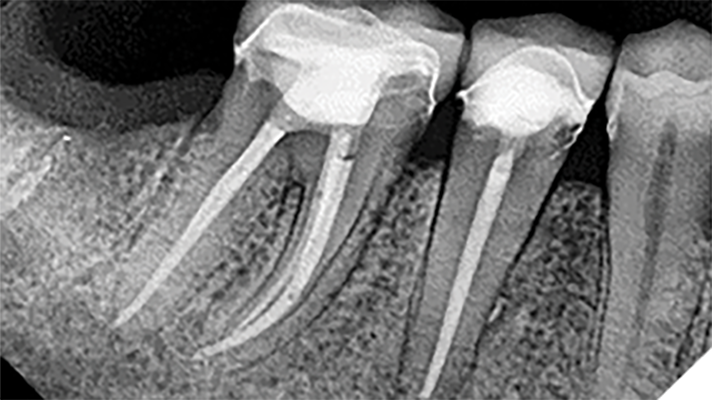

Deep Shape in Endodontics: Significance, Rationale and Benefit

The goal of endodontic treatment is to prevent or cure, when present, Lesions of Endodontic Origin, at times referred to as apical periodontitis. The role of bacteria in the pathogenesis of endodontic disease is well established, and therefore, it is critical to eradicate these pathogens by employing the highest level of presently developed standards. This … Read more